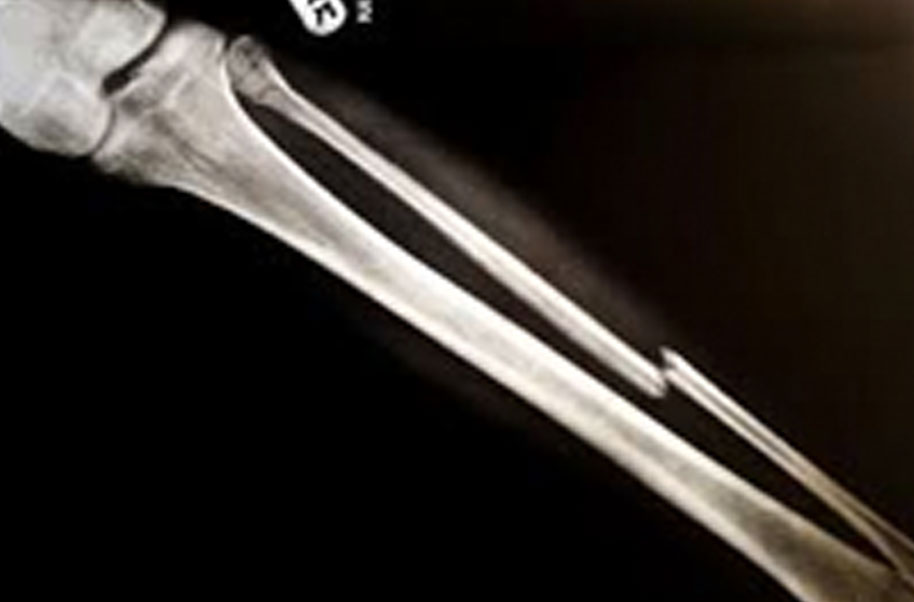

Membrane Bone (Broken Bone)

A complete or partial break in a bone.

- Treatment often involves resetting the bone in place and immobilising it in a cast or splint to give it time to heal. Sometimes, surgery with rods, plates and screws may be required.

Causes of bone fractures include trauma, overuse and diseases that weaken bones.